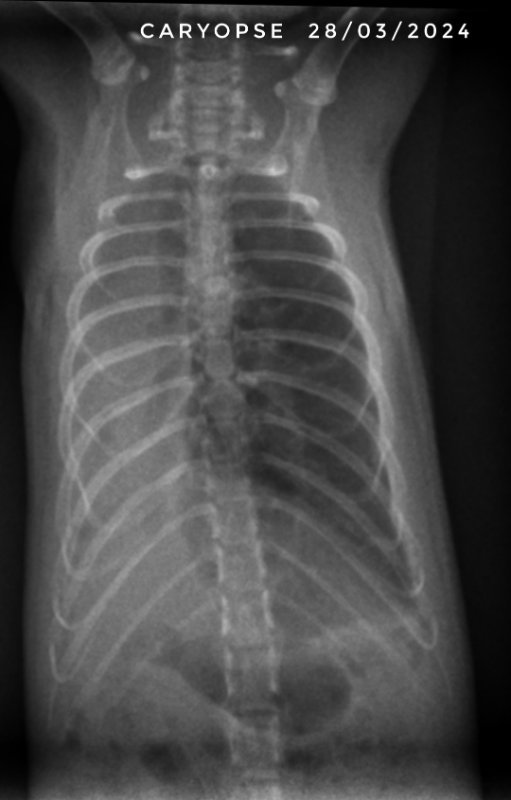

Et voici les dernières radios de Drupe. On est donc normalement sereins, les poumons ne sont pas parfaits, mais on est sûrement sur des cicatrices. Maintenant, il lui reste à passer l'étape de la castration et normalement ensuite il sera tranquille niveau soins vetos ^^

Le seul ayant eu du chloramphénicol est décédé. Pour les autres c'est le trio tylosine par nébu + doxycycline et azythromycine qui a été efficace. Après les filles ont eu très peu de symptômes (la plus touchée c'était ma petite Graine, que j'ai gardée donc, et qui n'a jamais eu les poumons touchés pour autant).